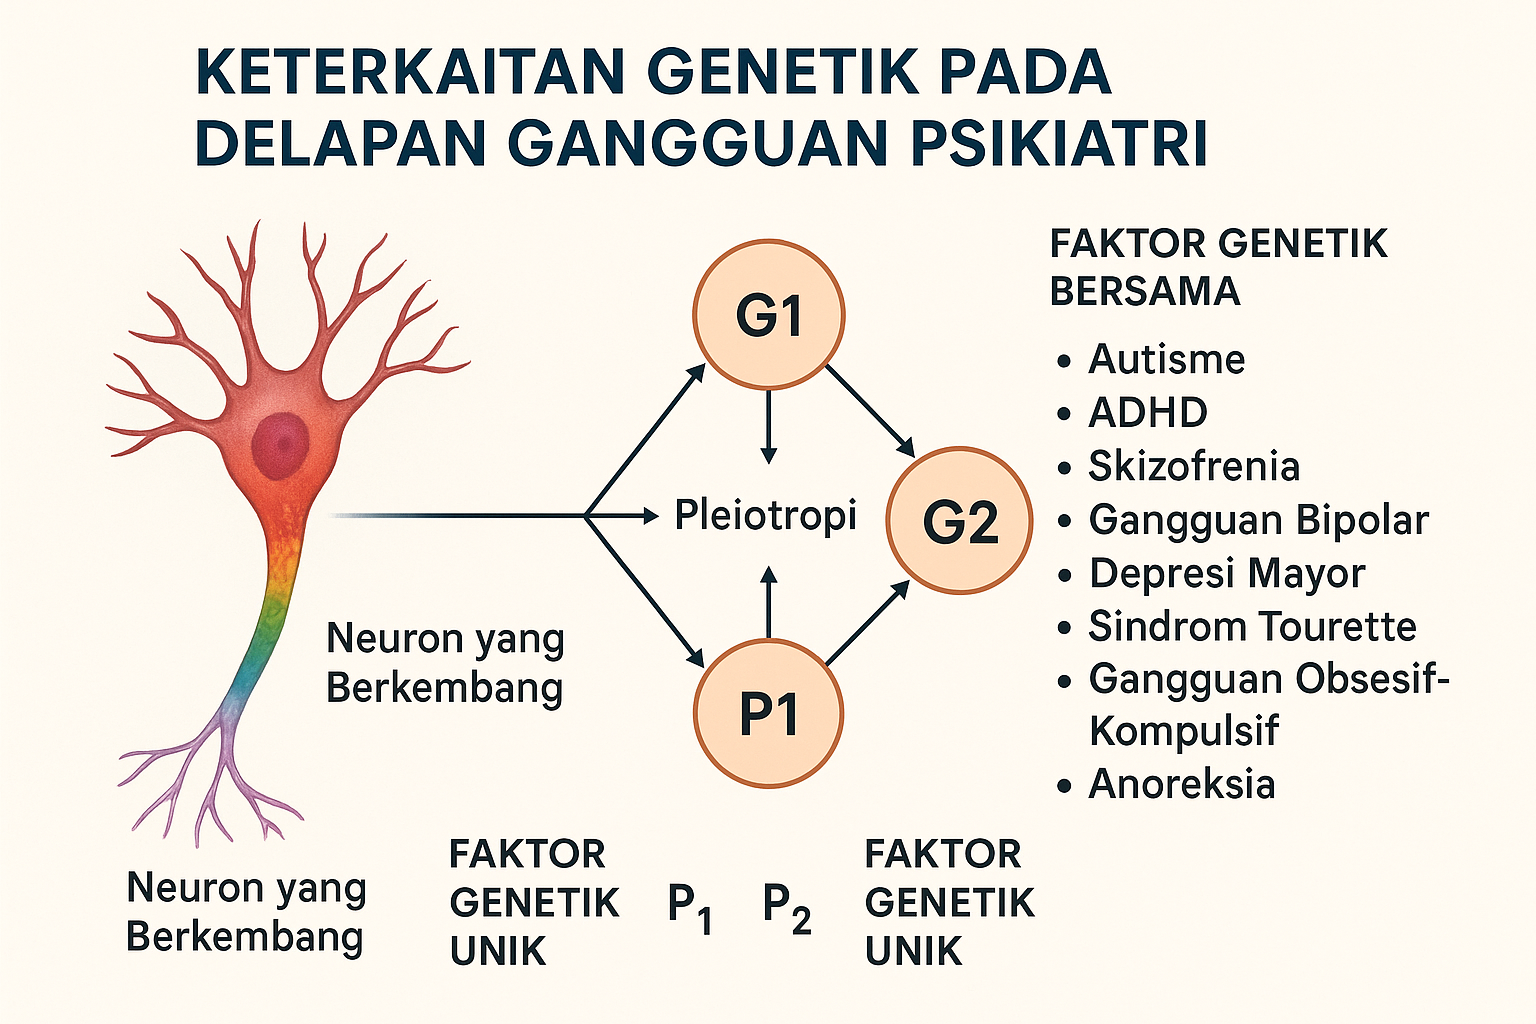

Tidak Ada ‘Gen Gay,’ Penelitian Utama Menyimpulkan

Tidak ada yang namanya "gen gay" tunggal yang memengaruhi perilaku seksual seseorang, demikiam kesimpulan sebuah studi genetik terbesar yang pernah dilakukan tentang masalah ini. Akan tetapi, ketertarikan seseorang terhadap mereka yang berjenis kelamin sama dibentuk oleh gabungan kompleks antara pengaruh genetik dan lingkungan, mirip dengan apa yang dapat ditemui pada sebagian besar sifat-sifat manusia yang lainnya, para peneliti melaporkan. "Ini merupakan...